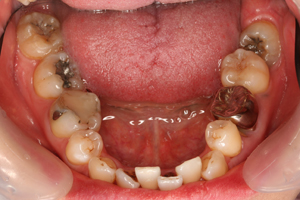

■口の中の金属を白くする症例

初診時

セット後